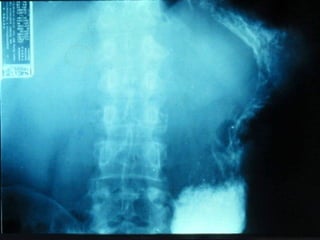

SEGD PATOLOGÍA ESOFÁGICA AFECCIONES DIVERSAS: Hernia de Hiato Divertículos Desgarro de Mallory Weiss y rotura esofágica

SEGD PATOLOGÍA ESOFÁGICAAFECCIONES DIVERSAS: Hernia de Hiato Divertículos Desgarro de Mallory Weiss y rotura esofágica